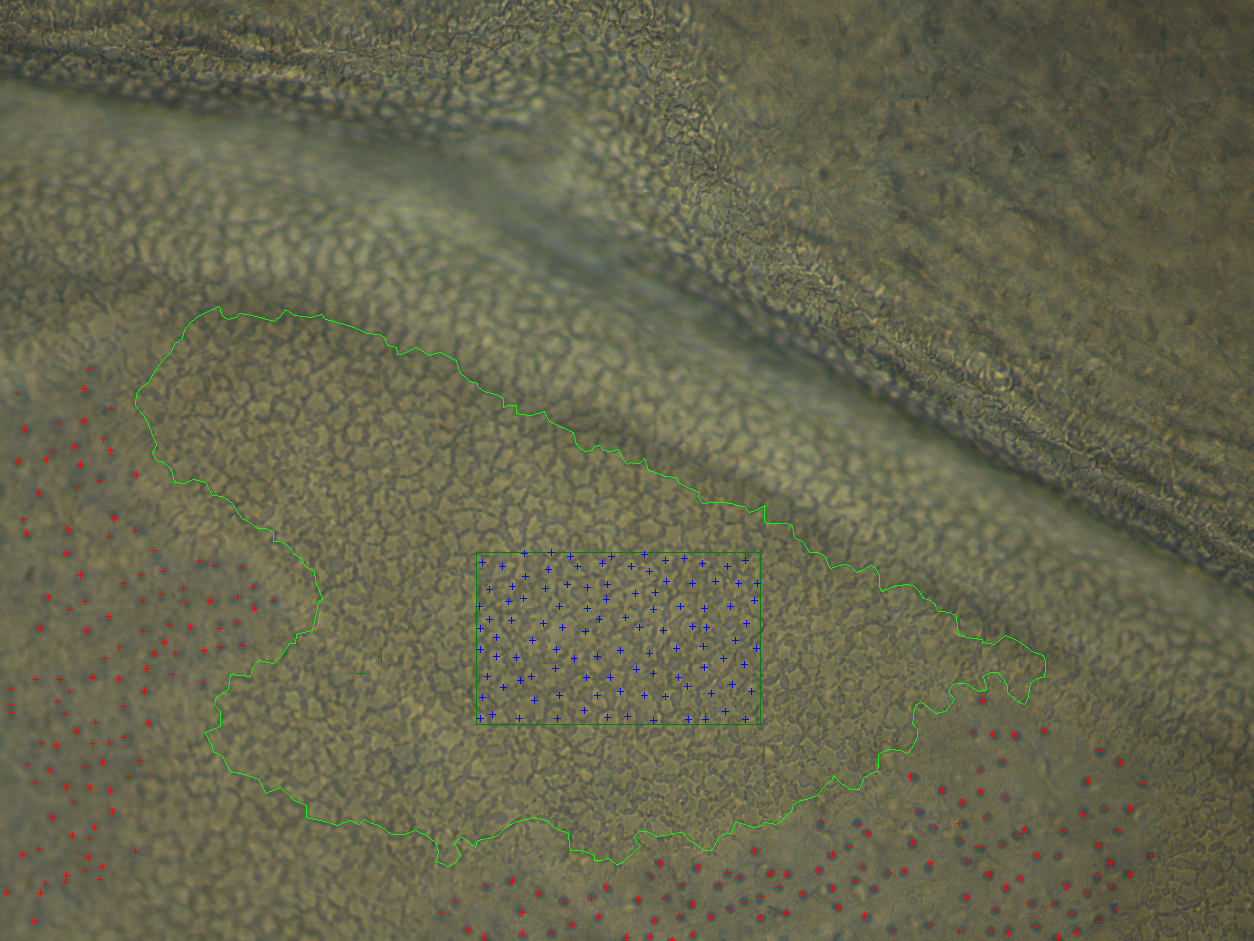

KerifAI utilise la vision par ordinateur et le deep learning pour identifier, compter, segmenter

et classifier les cellules endothéliales sur une surface représentative des tissus, améliorant

précision, reproductibilité et fiabilité. Les techniciens annotent les images de cornées pour

entraîner les algorithmes, qui permettent désormais de qualifier des tissus auparavant écartés